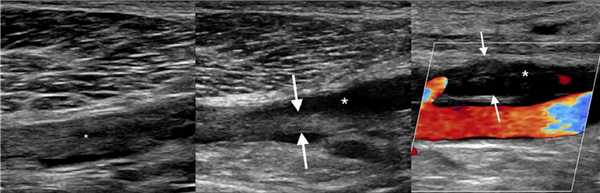

Задача. На УЗИ острый окклюзивный тромбоз ПБВ (1); спустя время ретракция сгустка и частичная реканализация (2).

Задача. На УЗИ острый окклюзивный тромбоз ПкВ (1); ретракция сгустка (2); рецидив тромбоза с окклюзией ПкВ (3).